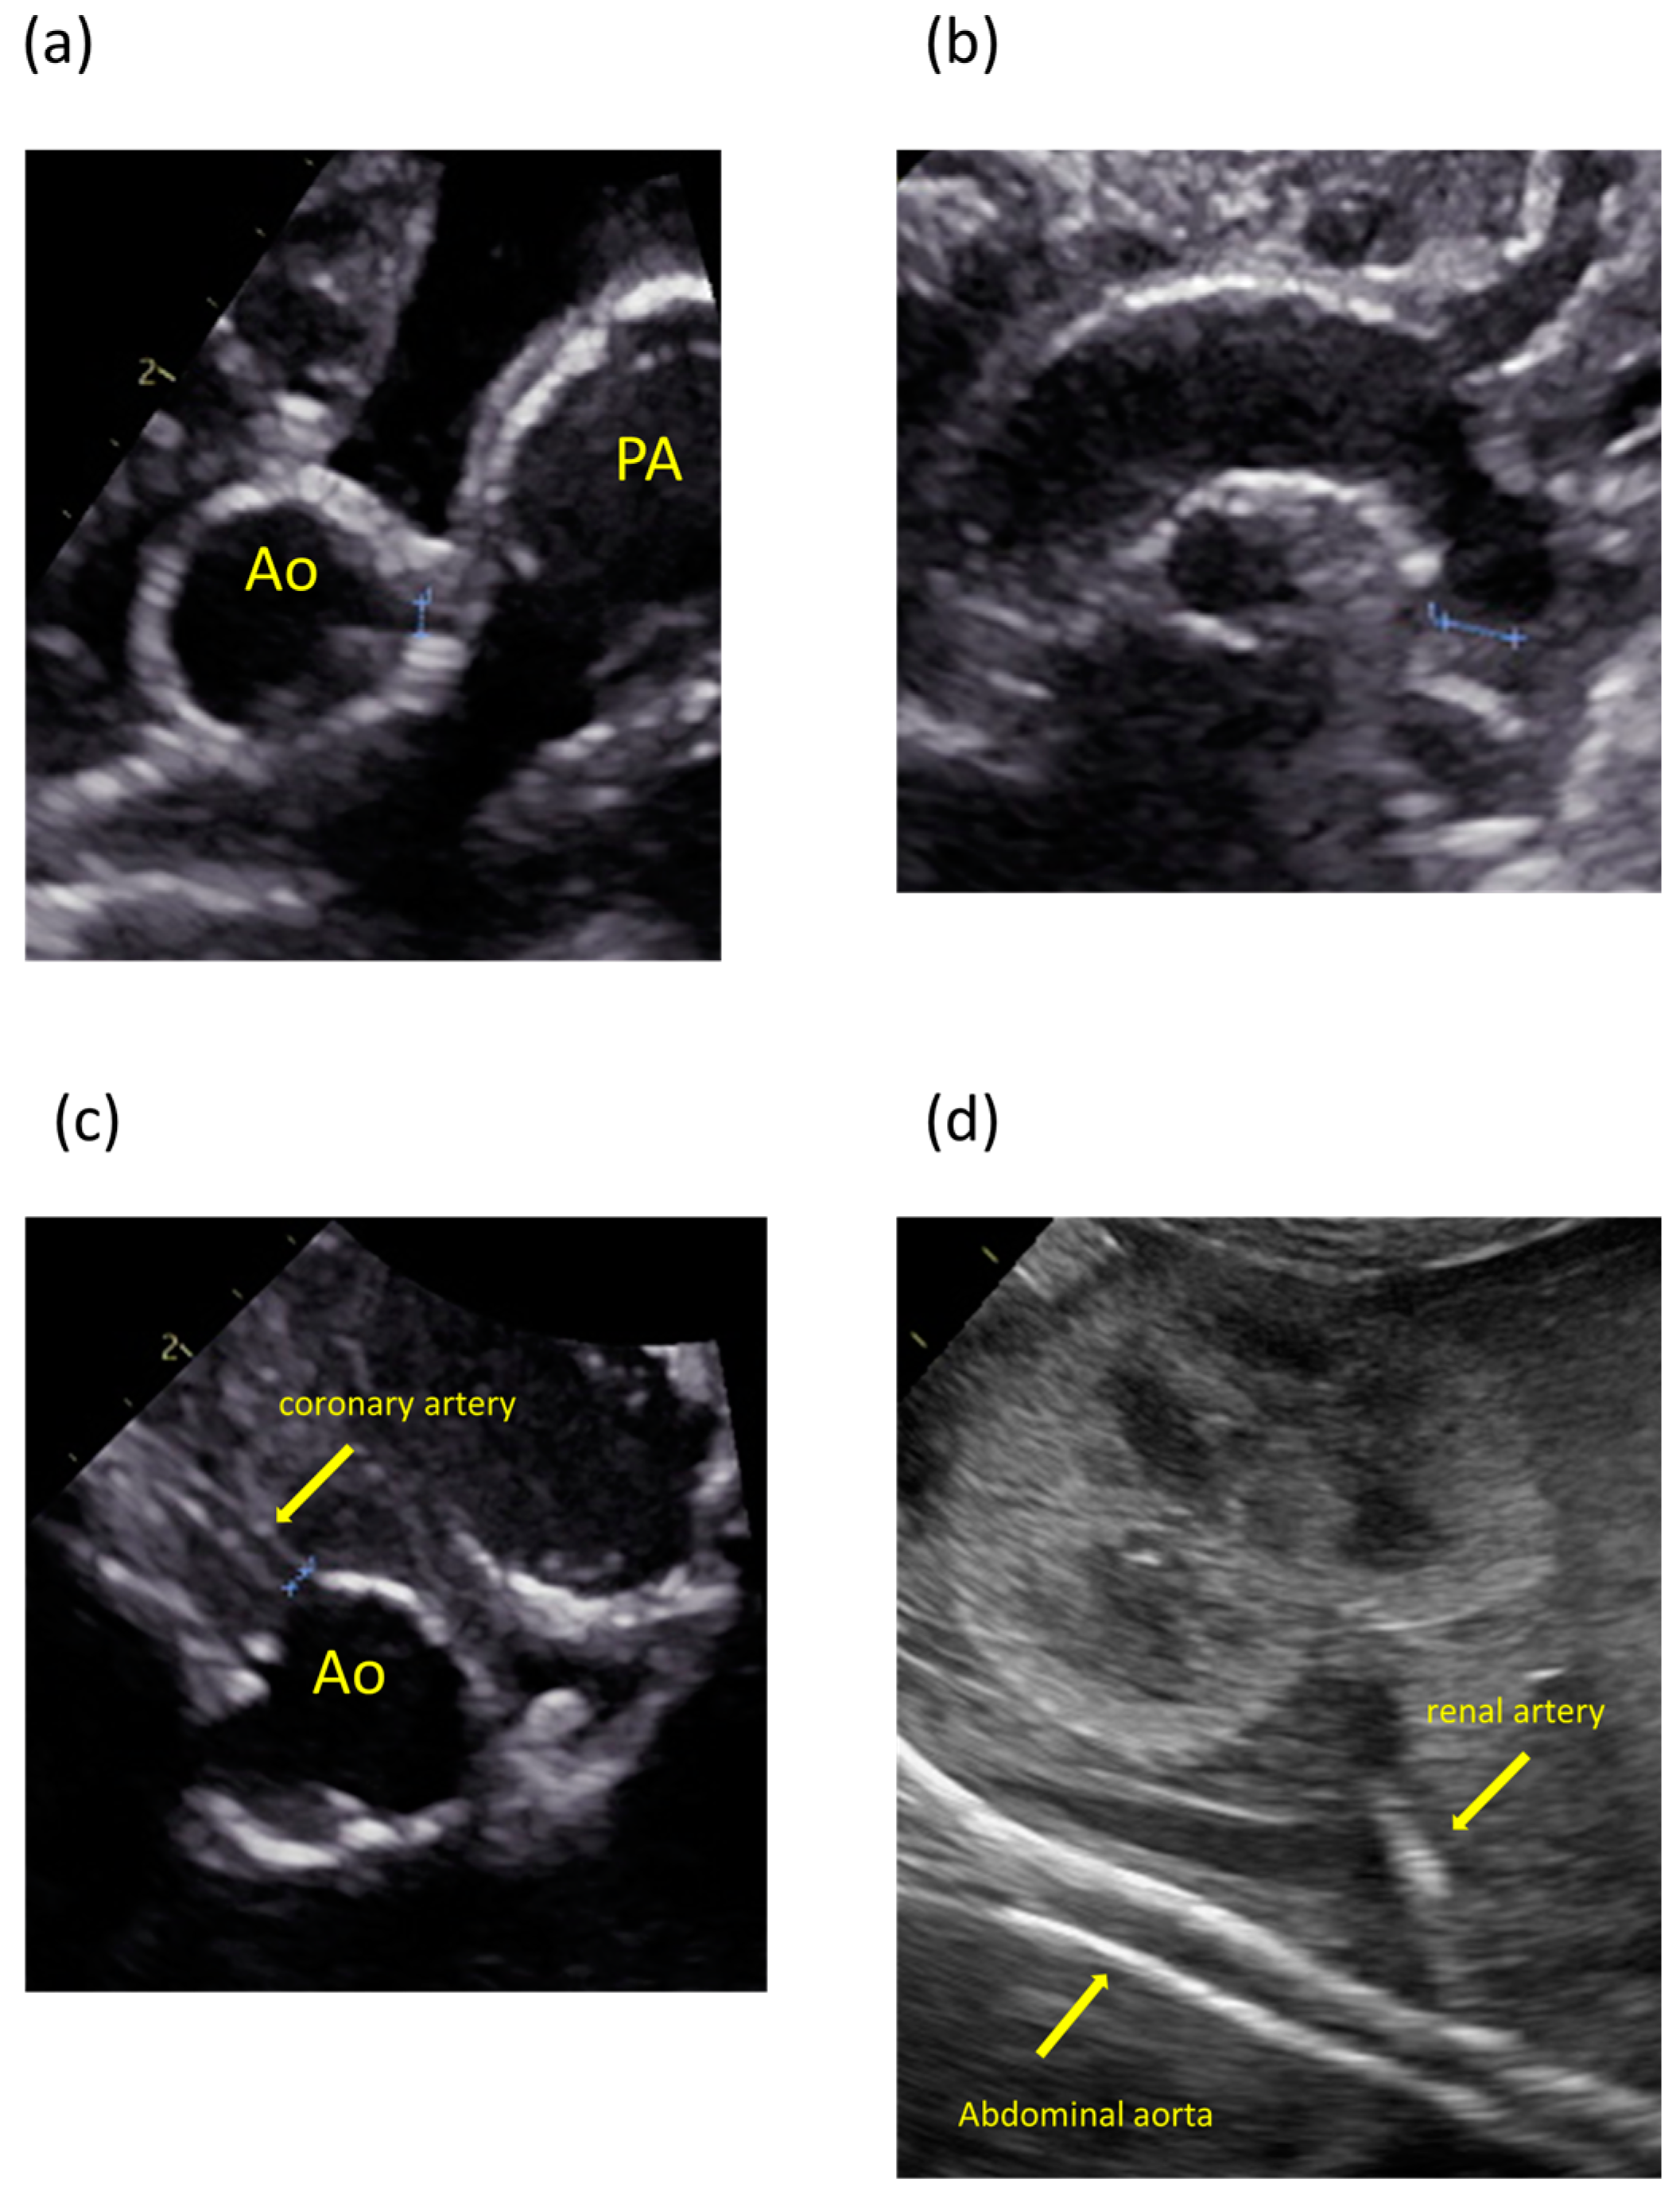

The patient was the second child of nonconsanguineous parents without a family history of the disease. The patient’s mother was a 35-year-old pregnant woman, gravida 2 para 1, and had no history of miscarriage. She was transferred to our hospital because fetal ultrasonography showed hydrops fetalis. Her obstetric history was unremarkable, without significant medical or surgical histories. There were no abnormalities at her prenatal checkups until 28 weeks of gestation. Fetal ultrasonography on admission revealed polyhydramnios, hydrops fetalis, and cardiac enlargement. Betamethasone was administered in preparation for premature delivery. A cesarian section was performed at 30 weeks of gestation because of non-reassuring fetal status. The patient was born with a birth weight of 1804 g. The Apgar scores were 1 and 3 at 1 and 5 min, respectively. The patient required resuscitation and tracheal intubation at birth due to respiratory distress syndrome. No dysmorphic features were observed. Postnatal ultrasonography showed enlargement of both ventricles and decreased cardiac contractility, with high-intensity lesions in the walls of the aorta, pulmonary artery, ductus arteriosus, and coronary artery (Figure 1). The blood pressure was markedly high (69/49 mmHg, upper 95th percentile).

Figure 1.

Ultrasonography images showing calcification and high-intensity lesions in the arterial walls. (a) Aorta and pulmonary artery. (b) Aortic arch. (c) Coronary artery. (d) Abdominal aorta and renal artery.

The arteries most frequently noted to be calcified in GACI are the aorta, hepatic artery, coronary artery, and renal artery [11]. Therefore, clinicians should suspect GACI when ultrasonography shows high-intensity lesions in these arteries. The present case also showed characteristic findings on ultrasonography. In early onset GACI, similar findings are detected in utero [12]. A review of the present patient’s medical records revealed that there was a high-intensity lesion of the aorta detected on fetal ultrasound. It is important to suspect GACI when a patient presents with unexplained hydrops, hypertension, heart failure, and persistent or enhanced high-intensity lesions of the arterial walls on ultrasound. If GACI can be diagnosed prenatally, appropriate counseling can be provided to the parents [13,14]. This would also lead to proper management of the fetus during pregnancy and early initiation of treatment after birth.